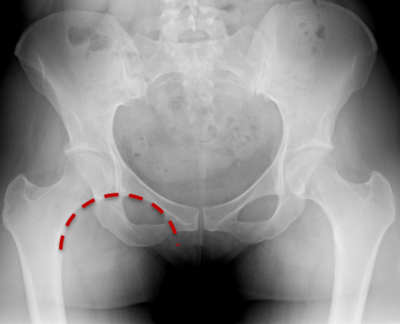

Question

The red line represents

Answer

• Kohler's line

• Shenton's line

• Skinner's Line

Which of the following is Shenton's line radiographic landmark used to assess?

• Offset

• Version

• Leg Length